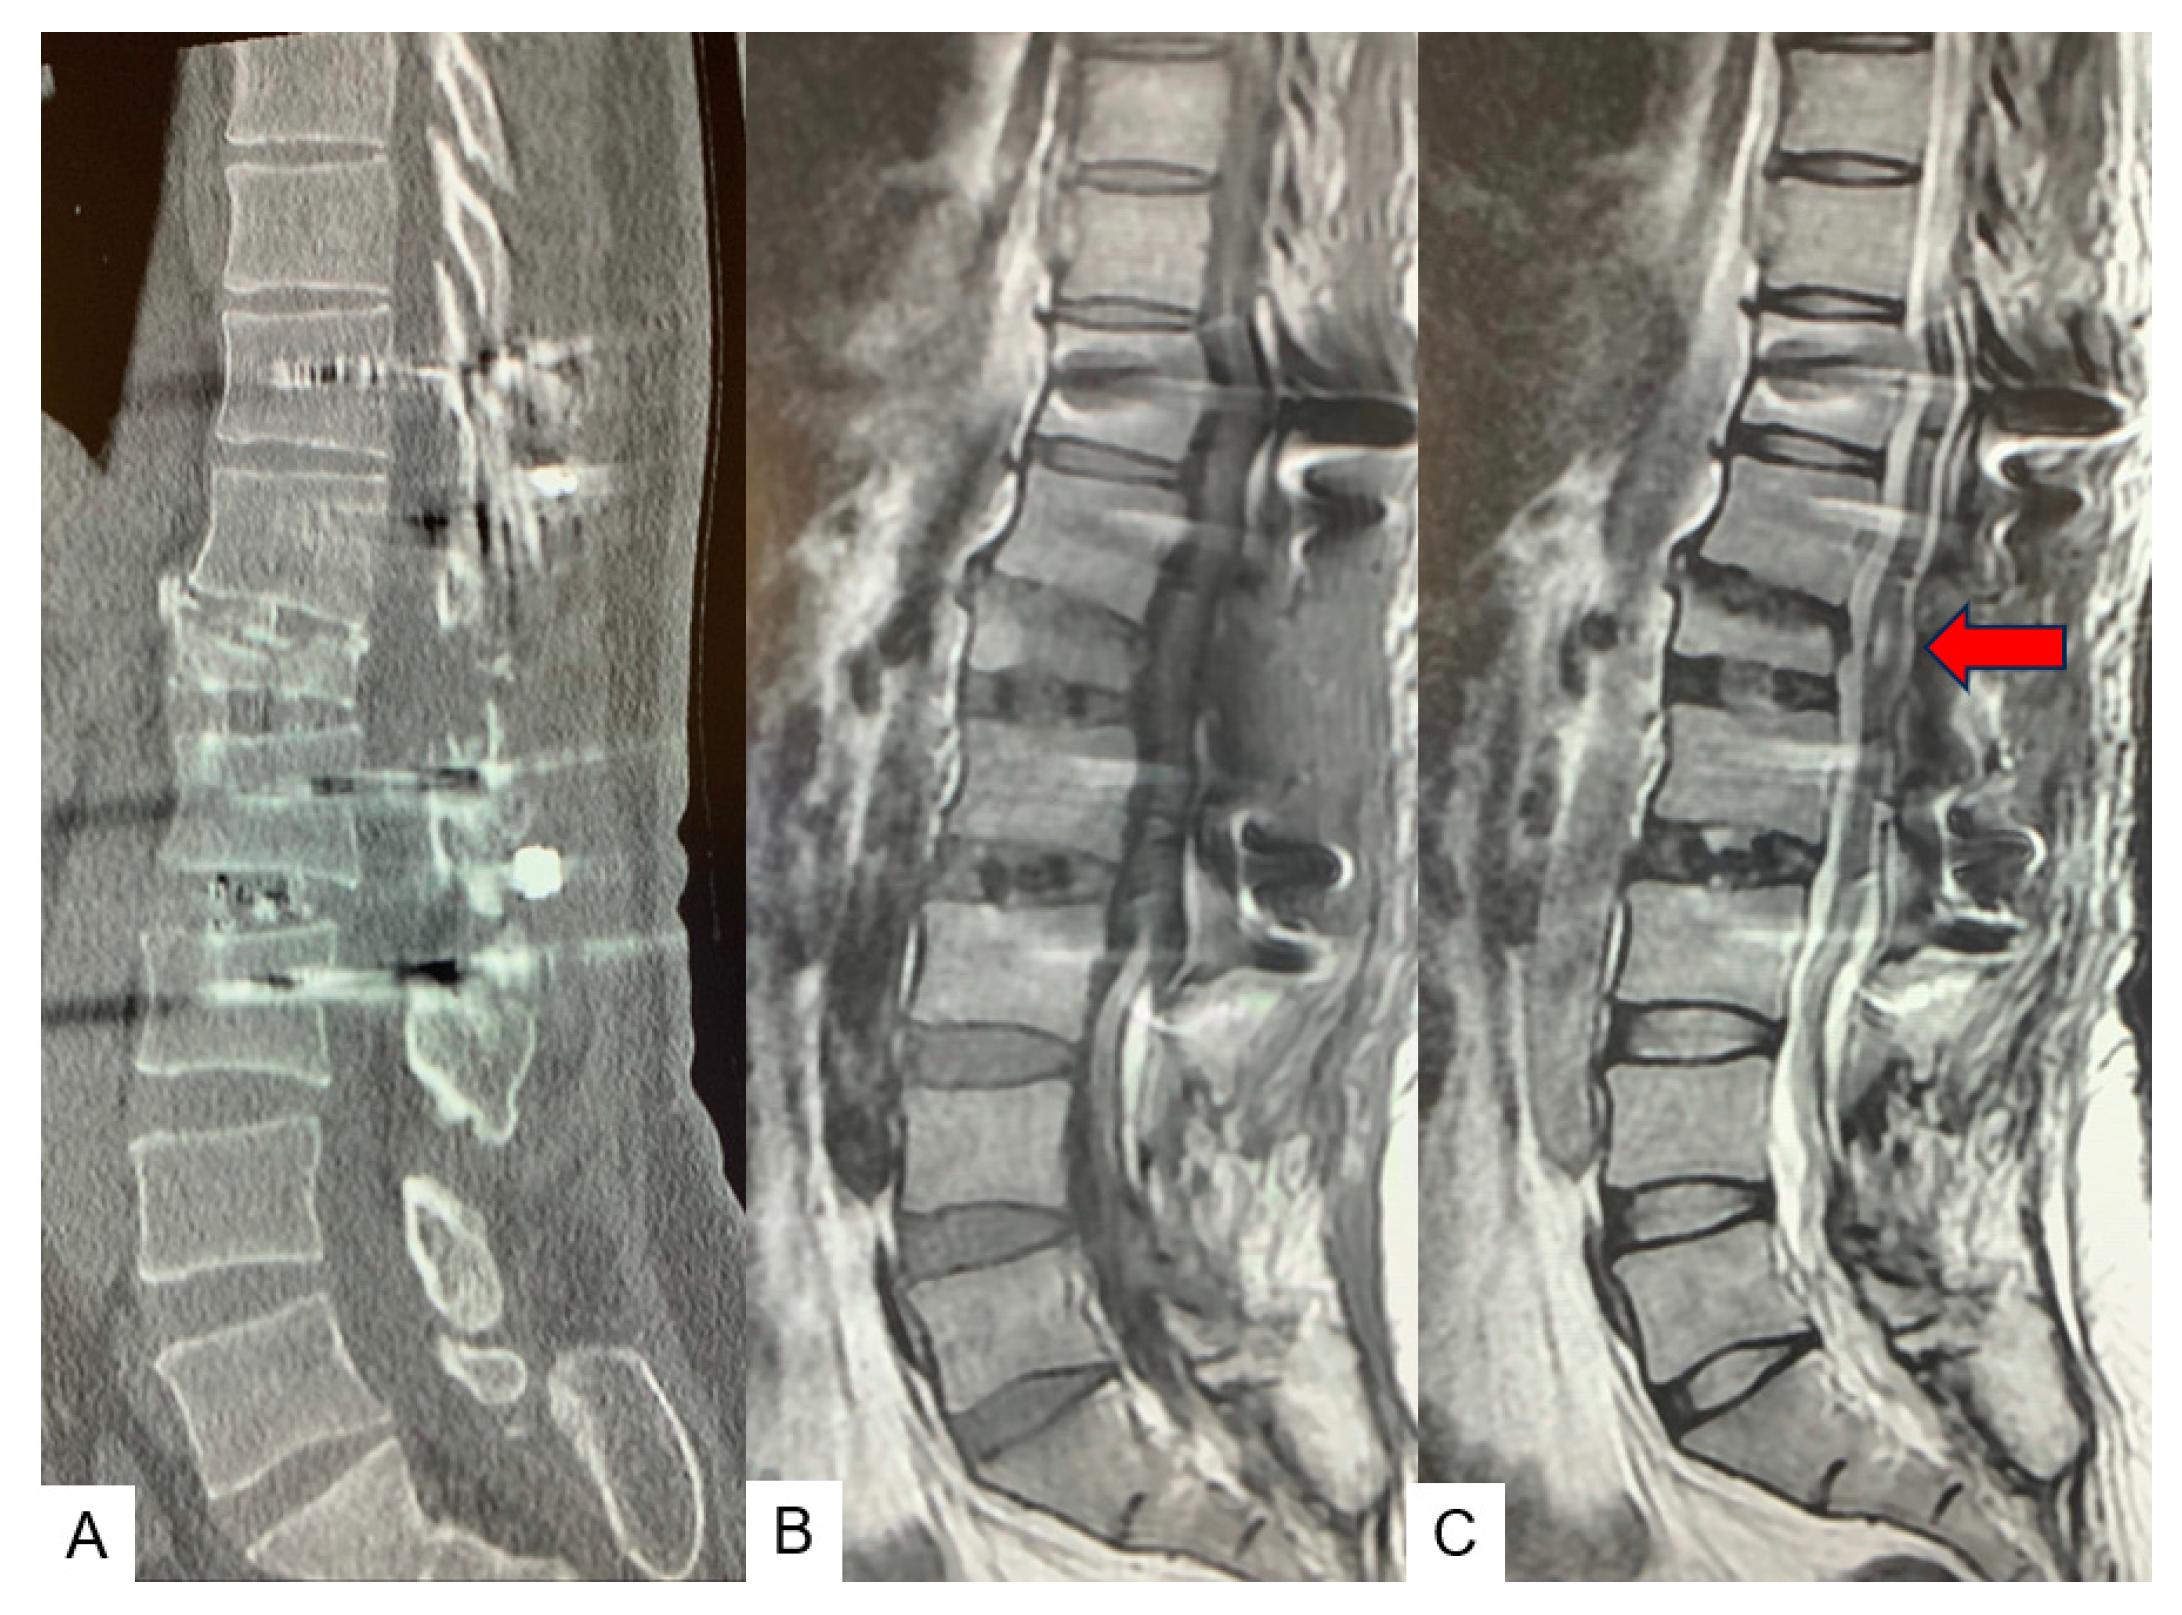

2.3. Preoperative Imaging

2.4. Surgery

2.5. Postoperative Images

2.6. One Year Follow-Up